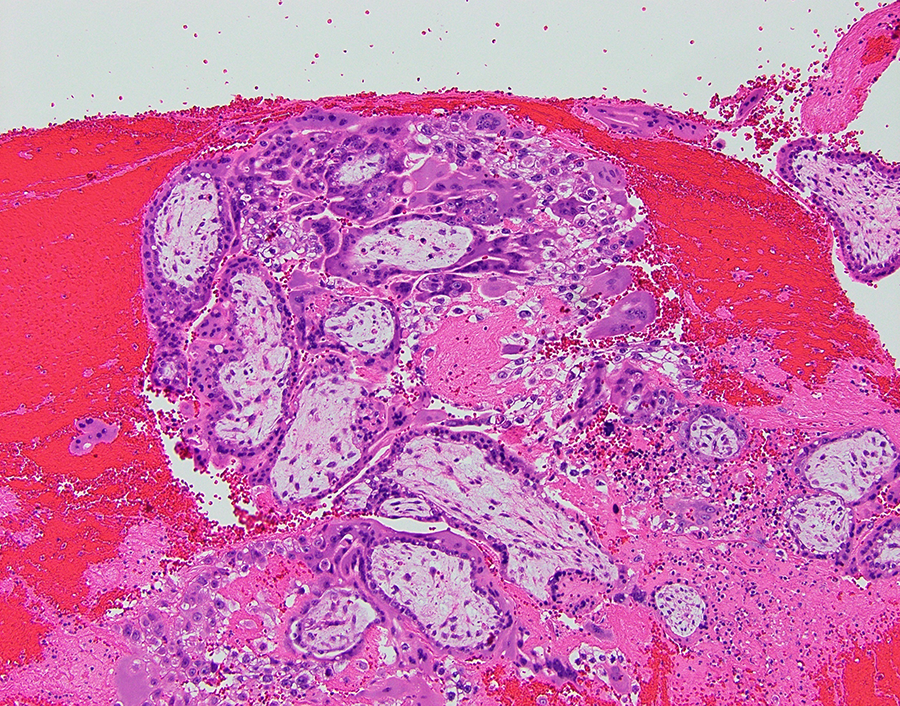

A tubal ectopic pregnancy can be grossly described as a distended fallopian tube with a thin wall, which may be ruptured, with dusky and dark serosa (Figure 3). Sectioning usually reveals hemorrhage with villous-appearing tissue. Fetal parts may be seen occasionally (Figure 4). On histology, chorionic villi associated with the fallopian tube is diagnostic of an ectopic pregnancy (Figures 5 and 6). Hemorrhage within the tubal lumen is often present.

Intraluminal immature chorionic villi with edematous stroma and surrounding trophoblasts. The presence of villi within the fallopian tube is diagnostic of a tubal (ectopic) pregnancy. H&E-stained section at ×100.

Histologically, the presence of chorionic villi within the tubal epithelium is diagnostic of a tubal ectopic pregnancy.